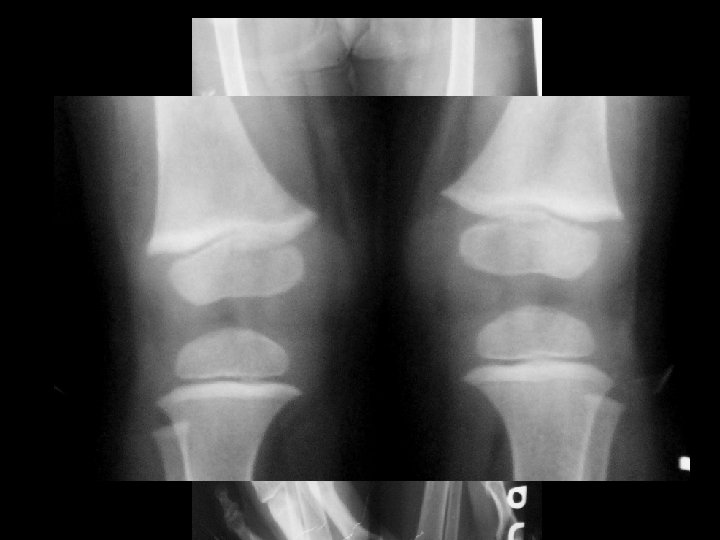

The Dense Metaphyseal Band Sign • Dense metaphyseal bands, less commonly known as dense metaphyseal lines, transverse bands, or "lead lines, " indicate radiopaque bone (thicker than the adjacent diaphyseal cortex) at the metaphysis of growing bone, particularly at the wrists and knees.

Anteroposterior radiograph of the wrist obtained in a 2 -year-old boy reveals a dense metaphyseal band (arrow) in the distal radius, without flaring or cupping. The distal ulna is unremarkable. By excluding more serious causes, this finding was proved to be a normal variant.

Anteroposterior radiograph of the knees in a 4 -year-old girl reveals very dense metaphyseal bands in the distal femurs and proximal tibias (arrows) as well as in the proximal fibulas (arrowheads). This patient was encephalopathic and anemic and had a lead level of 60 µg/d. L (2. 898 µmol/L) at admission.

• 1) 2) 3) 4) 5) In order of decreasing frequency, the causes of a dense metaphysis include Normal variance ( most common cause) Plumbism, Treated leukemia, Healing rickets, Other heavy metal (arsenic, bismuth, mercury) poisoning, 6) Recovery from scurvy, vitamin D hypervitaminosis, 7) Congenital hypothyroidism, hypoparathyroidism, and 8) Transplacental infections (eg, toxoplasmosis, rubella, cytomegalovirus, and herpes).

• Lead poisoning in infants and children may be diagnosed in screening programs, clinically, or radiographically. • Plumbism in children can be traced to pica (eg, dirt eating), acute ingestion of lead-based paints, consumption of home remedies, inhalation of toxic fumes, and rarely, absorption of lead-containing material from metallic or bullet fragments in a serous cavity or joint. • In general, lead lines indicate past lead exposure and correlate with a blood lead level of 50 µg/d. L. • The presence of a dense metaphyseal band at the proximal fibula is a strong indication of plumbism, although the mechanism related to the lead toxicity remains unknown.

• The presence of dense metaphyseal bands strongly supports the diagnosis of lead toxicity. • With treatment or cessation of lead exposure, the lead band will demonstrate an apparent migration into the metadiaphysis because of normal new bone growth. • Accordingly, when the lead level returns to normal, the metaphyseal band will gradually decrease in radiopacity and disappear in approximately 4 years.

• Knee of a 3 -year-old girl with leukemia. Anteroposterior radiograph shows formation of thin, dense metaphyseal bands (growth recovery lines) In femur and tibia and less so In fibula, owing to cycles of chemotherapy. n Normal knee of a 2 month- old boy. Anteroposterlor radiograph shows normal sclerotic lines of distal femoral and proximal tiblal metaphyses. These should not be confused with bands caused by chronic Ingestion of heavy metals. Note absence of sclerosis of proximal part of flbula.

Knee of a 4 -year-old boy with lead poisoning. A, Initial anteroposterior radiograph shows a thick, radlopaque metaphyseal band across femur, tibia, and fibula. B, Radiograph obtained 6 months after A shows growth plate has moved away from original prominent radiopaque band. New band suggests a recurrent episode of lead ingestion. Radlopaque metaphyseal band (arrow) In proximal part of fibula and other nonweight-bearing bones Is particularly suggestive of heavy-metal poisoning.